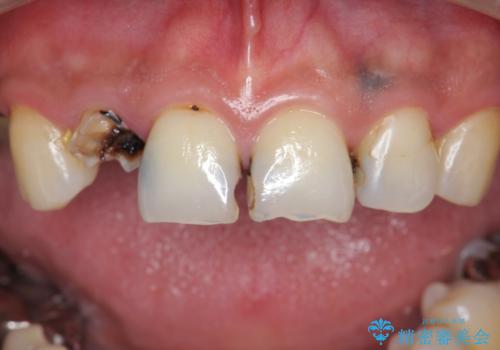

「 放置した虫歯 」 前歯セラミック治療

- 前歯の虫歯に気付きながらも放置し、一念発起し治療を希望され来院されました。

虫歯のマイクロスコープによる丁寧な除去、根管治療、深い虫歯に対する挺出(エクストリュージョン)および歯周外科を行ったのち精度の高いセラミッククラウン製作治療を計画します。

虫歯の放置により、根管治療や深い虫歯に対する処置が必要になりましたが丁寧に一つづつ処置を行ったことで抜歯をすることなく歯を残すことができました。